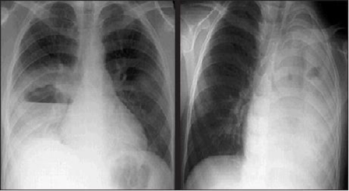

Chẩn đoán được nghĩ đến thông qua hình ảnh hang có thành dày với mức khí dịch (hình 1) trên X-quang phổi, và được xác định với hình ảnh CT-scan cản quang. Áp-xe phổi thường kèm với tràn dịch màng phổi.

Hình 1: Hình ảnh X-quang biến chứng của viêm phổi phế cầu. Hình bên trái: Áp-xe phổi với mức khí dịch ở phổi bên phải. Hình bên phải: viêm phổi hoại tử ở phổi trái.